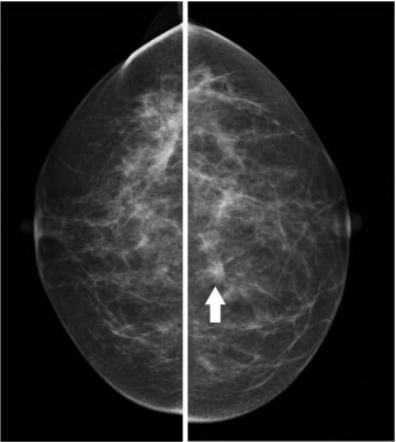

Cicatriz radial. Mujer de 48 años, asintomática. Mamografía digital. En cuadrantes internos de mama izquierda se identificó una lesión espiculada junto con distorsión parenquimatosa (flecha), criterios sospechosos de malignidad. Se realizó BAG y posteriormente extirpación quirúrgica, con resultado de cicatriz radial.